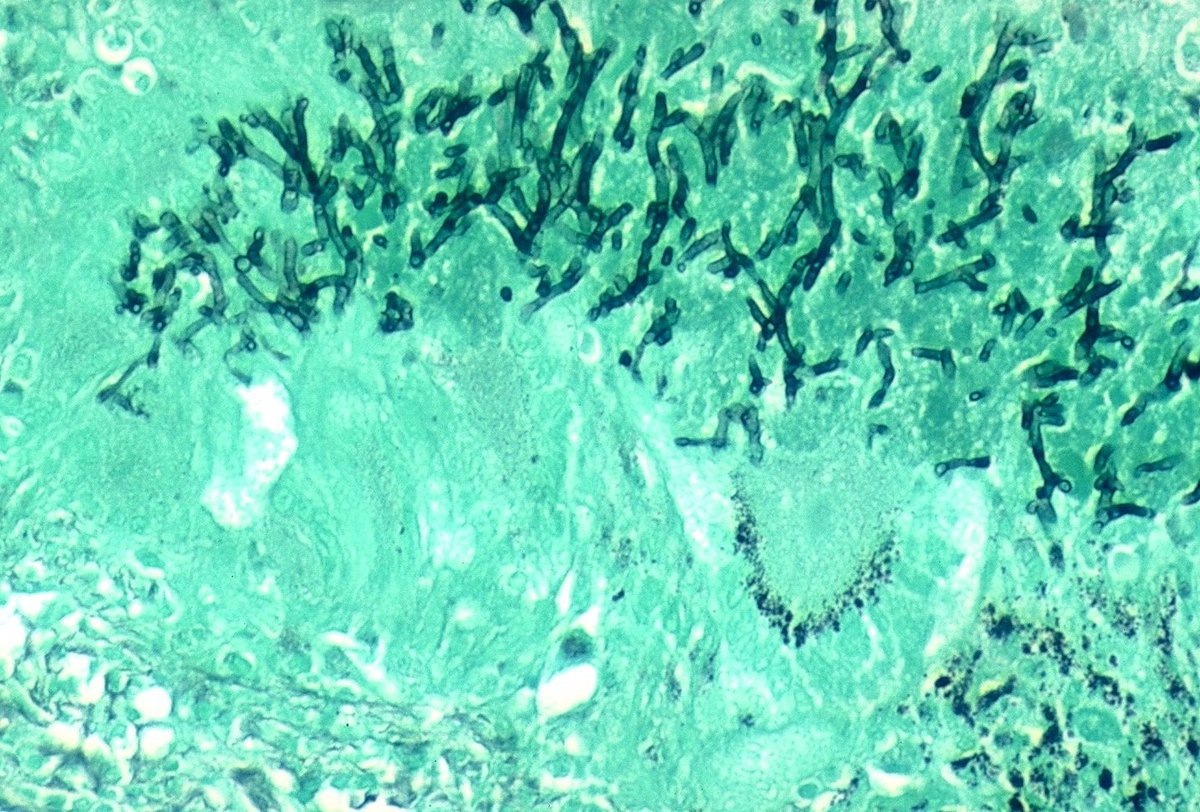

Invasive pulmonary

#aspergillosis with granulomatous inflammatory reaction.#pulmpath#fungi#granuloma pic.twitter.com/42lFrIkCDa